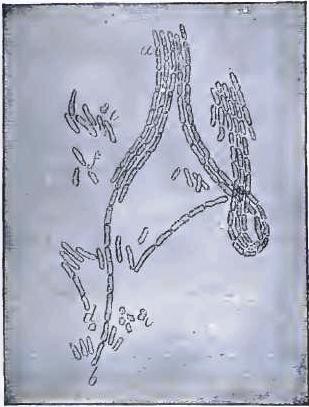

| FIGURE | |

| 7. | BACILLI FROM SWAMP-MUD |

| 8. | BACILLI FROM SEPTICÆMIC RABBIT |

| 9. | BACILLI FROM HUMAN SALIVA |

| 10. | BACILLUS ANTHRACIS |

| 11. | BACILLUS TUBERCULOSIS |